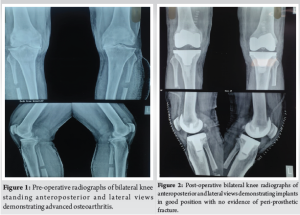

A 64-year-old male presented with complaints of bilateral knee pain and difficulty in activities of daily living for the past 5 years. He was a known diabetic on treatment. There was no history of any known allergies. Radiographs revealed bilateral end-stage osteoarthritis of the knee (Fig. 1). He had undergone a bilateral proximal fibular osteotomy 2 years prior for similar complaints. The patient was planned for bilateral total knee replacement after an anesthetist’s clearance. He was taken up for surgery under pneumatic tourniquet control. The tourniquet time for the right knee was 100 min, and for the left knee was 90 min. The skin was prepared with chlorhexidine and betadine solution. An OPSITE adherent dressing was applied over both knees. The medial parapatellar approach was used. Exactech cruciate retaining cemented implants were used in both knees. The surgery went uneventfully. Ranawat cocktail containing bupivacaine (0.5%), morphine sulphate (8 mg), epinephrine (1:1000), methylprednisolone acetate (40 mg), and cefuroxime (1.5 g) was infiltrated in the posterior capsule and gutters. The skin was closed with a suction drain inside, and a sterile dressing with cotton gauze piece and gamjee pad was done. The tourniquet was deflated once dressings were applied. Routine deep venous thrombosis prophylaxis injection enoxaparin 40 mg subcutaneously was started.

On post-operative day 2, a first wound inspection was performed with the removal of the drain. Multiple hemorrhagic blisters overlying erythematous skin, located adjacent to the surgical incision, were found over the left leg. Two to three clear, fluid-filled blisters overlying erythematous skin were found over the right leg (Fig. 3). Post-operative X-rays revealed a well-sited implant with no evidence of peri-implant fractures (Fig. 2). Distal pulses were intact postoperatively. Ultrasound venous Doppler images of both lower limbs showed no evidence of deep vein thrombosis. Biochemical markers of infection (C-reactive protein, TWC??) were unremarkable. What were the hemoglobin and platelet levels, and were any coagulation studies performed? Collagen dressings were applied over the blister site. Two to three large blisters were deroofed. Loose non-adherent dressings were done on both legs. Prophylactic intravenous cefuroxime 1.5 g was initiated and continued for 10 days to prevent infection. No further antibiotics were prescribed beyond this. Knee range of motion (ROM) exercises were initiated as tolerated by the patient. Full weight bearing was initiated on the 2nd post-operative day.